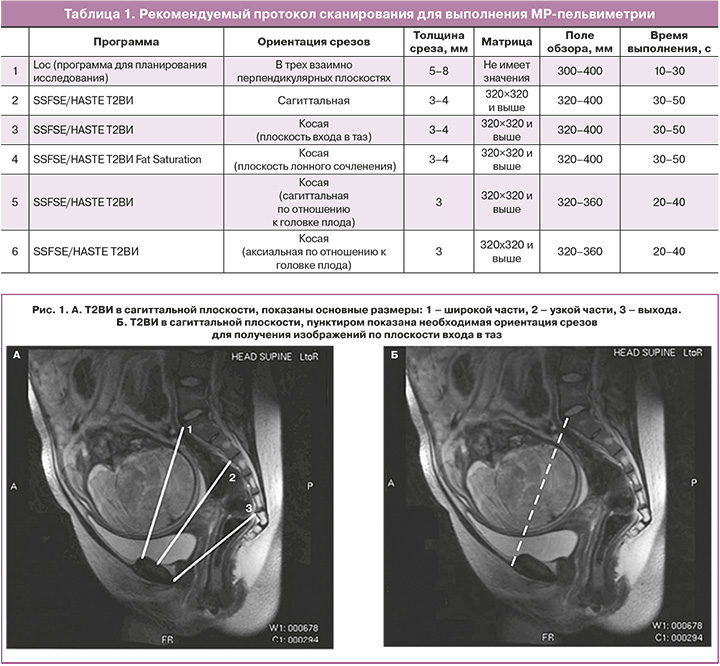

Исследование проводится на МР-томографах с индукцией поля 1,5 и 3Т по следующему протоколу (табл. 1). Рекомендуемые сроки проведения: III триместр, оптимально – после 36 недель. Используют импульсные последовательности (одноимпульсное, быстрое спин-эхо – SSFSE, HASTE). Продолжительность исследования составляет 5–10 минут. Результатами исследования служат полученные внутренние размеры таза, лобно-затылочный и битемпоральный размеры головки плода, а также выявленные признаки симфизита, наличия экзостозов, последствий травматического повреждения костей таза, копчика и их деформация, идиопатических переломов боковых масс крестца.

3. Т2-взвешенные изображения (Т2ВИ) (SSFSE/HASTE) в сагиттальной плоскости (по отношению к осям тела), толщина среза 3–4 мм, матрица квадратная не менее 320×320, поле обзора 320–400 мм (рис. 1). Сагиттальные томограммы служат для измерения прямых размеров таза: входа, широкой части полости, узкой части полости, выхода (расстояние от нижнего края лонного сочленения до копчика), длины и деформации копчика и кривизны крестца. Все измерения проводятся на срединном срезе, проходящем через лонное сочленение.

4. Т2ВИ (SSFSE/HASTE) в косой поперечной плоскости (плоскость входа в таз), толщина среза 3–4 мм, матрица квадратная не менее 320×320, поле обзора 300–340 мм томограммы позиционируют, как показано на рисунке 1, с использованием полученных сагиттальных срезов параллельно linea innominata. На полученных томограммах измеряют поперечные размеры таза: наибольший размер входа, широкой части, межостного, битуберозного (рис. 2).